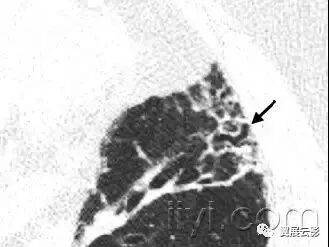

十八、小叶中心性:

解剖:小叶中心性用于描述次级肺小叶的支气管血管束中心区域。病理学上也用这一术语描述终末小支气管远端,位于呼吸性细支气管和肺泡管中心的病变。

CT:正常次级肺小叶中心的点状或者线状的密度增高影,胸膜下25px范围内最明显,代表小叶内的动脉,直径约1mm。

小叶中心性异常包括(1)结节(2)树芽征,提示小气道病变(3)由于临近间质的增厚或者浸润导致小叶中心结果更加清晰(4)小叶中心性肺气肿导致的异常低密度。

附图为小叶中心性肺气肿